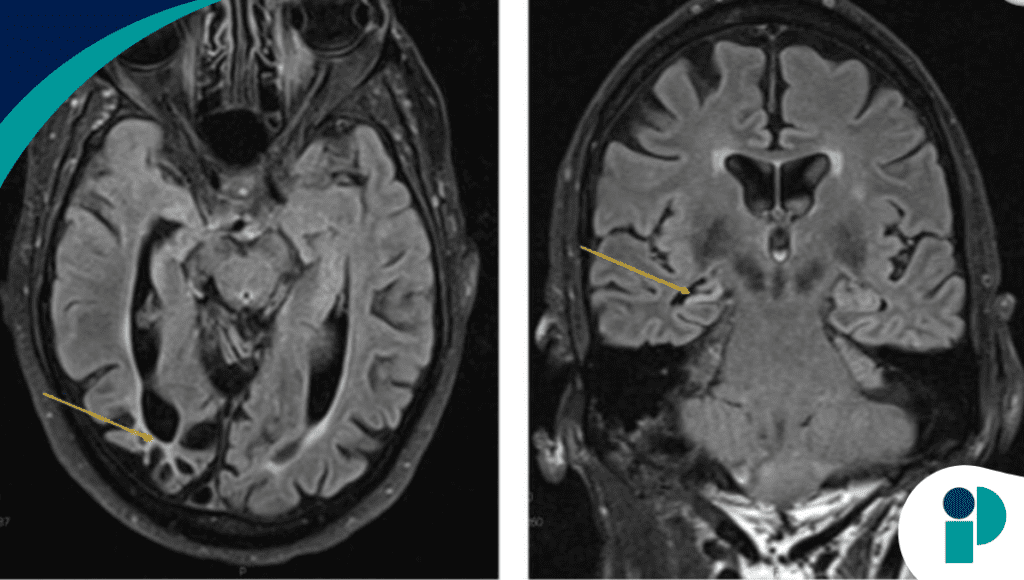

Los estudios de neuroimagen revelaron atrofia cortical posterior bilateral, daño occipito-parietal y esclerosis mesial temporal derecha, hallazgos que respaldan la asociación entre epilepsia del lóbulo temporal y cambios conductuales complejos.